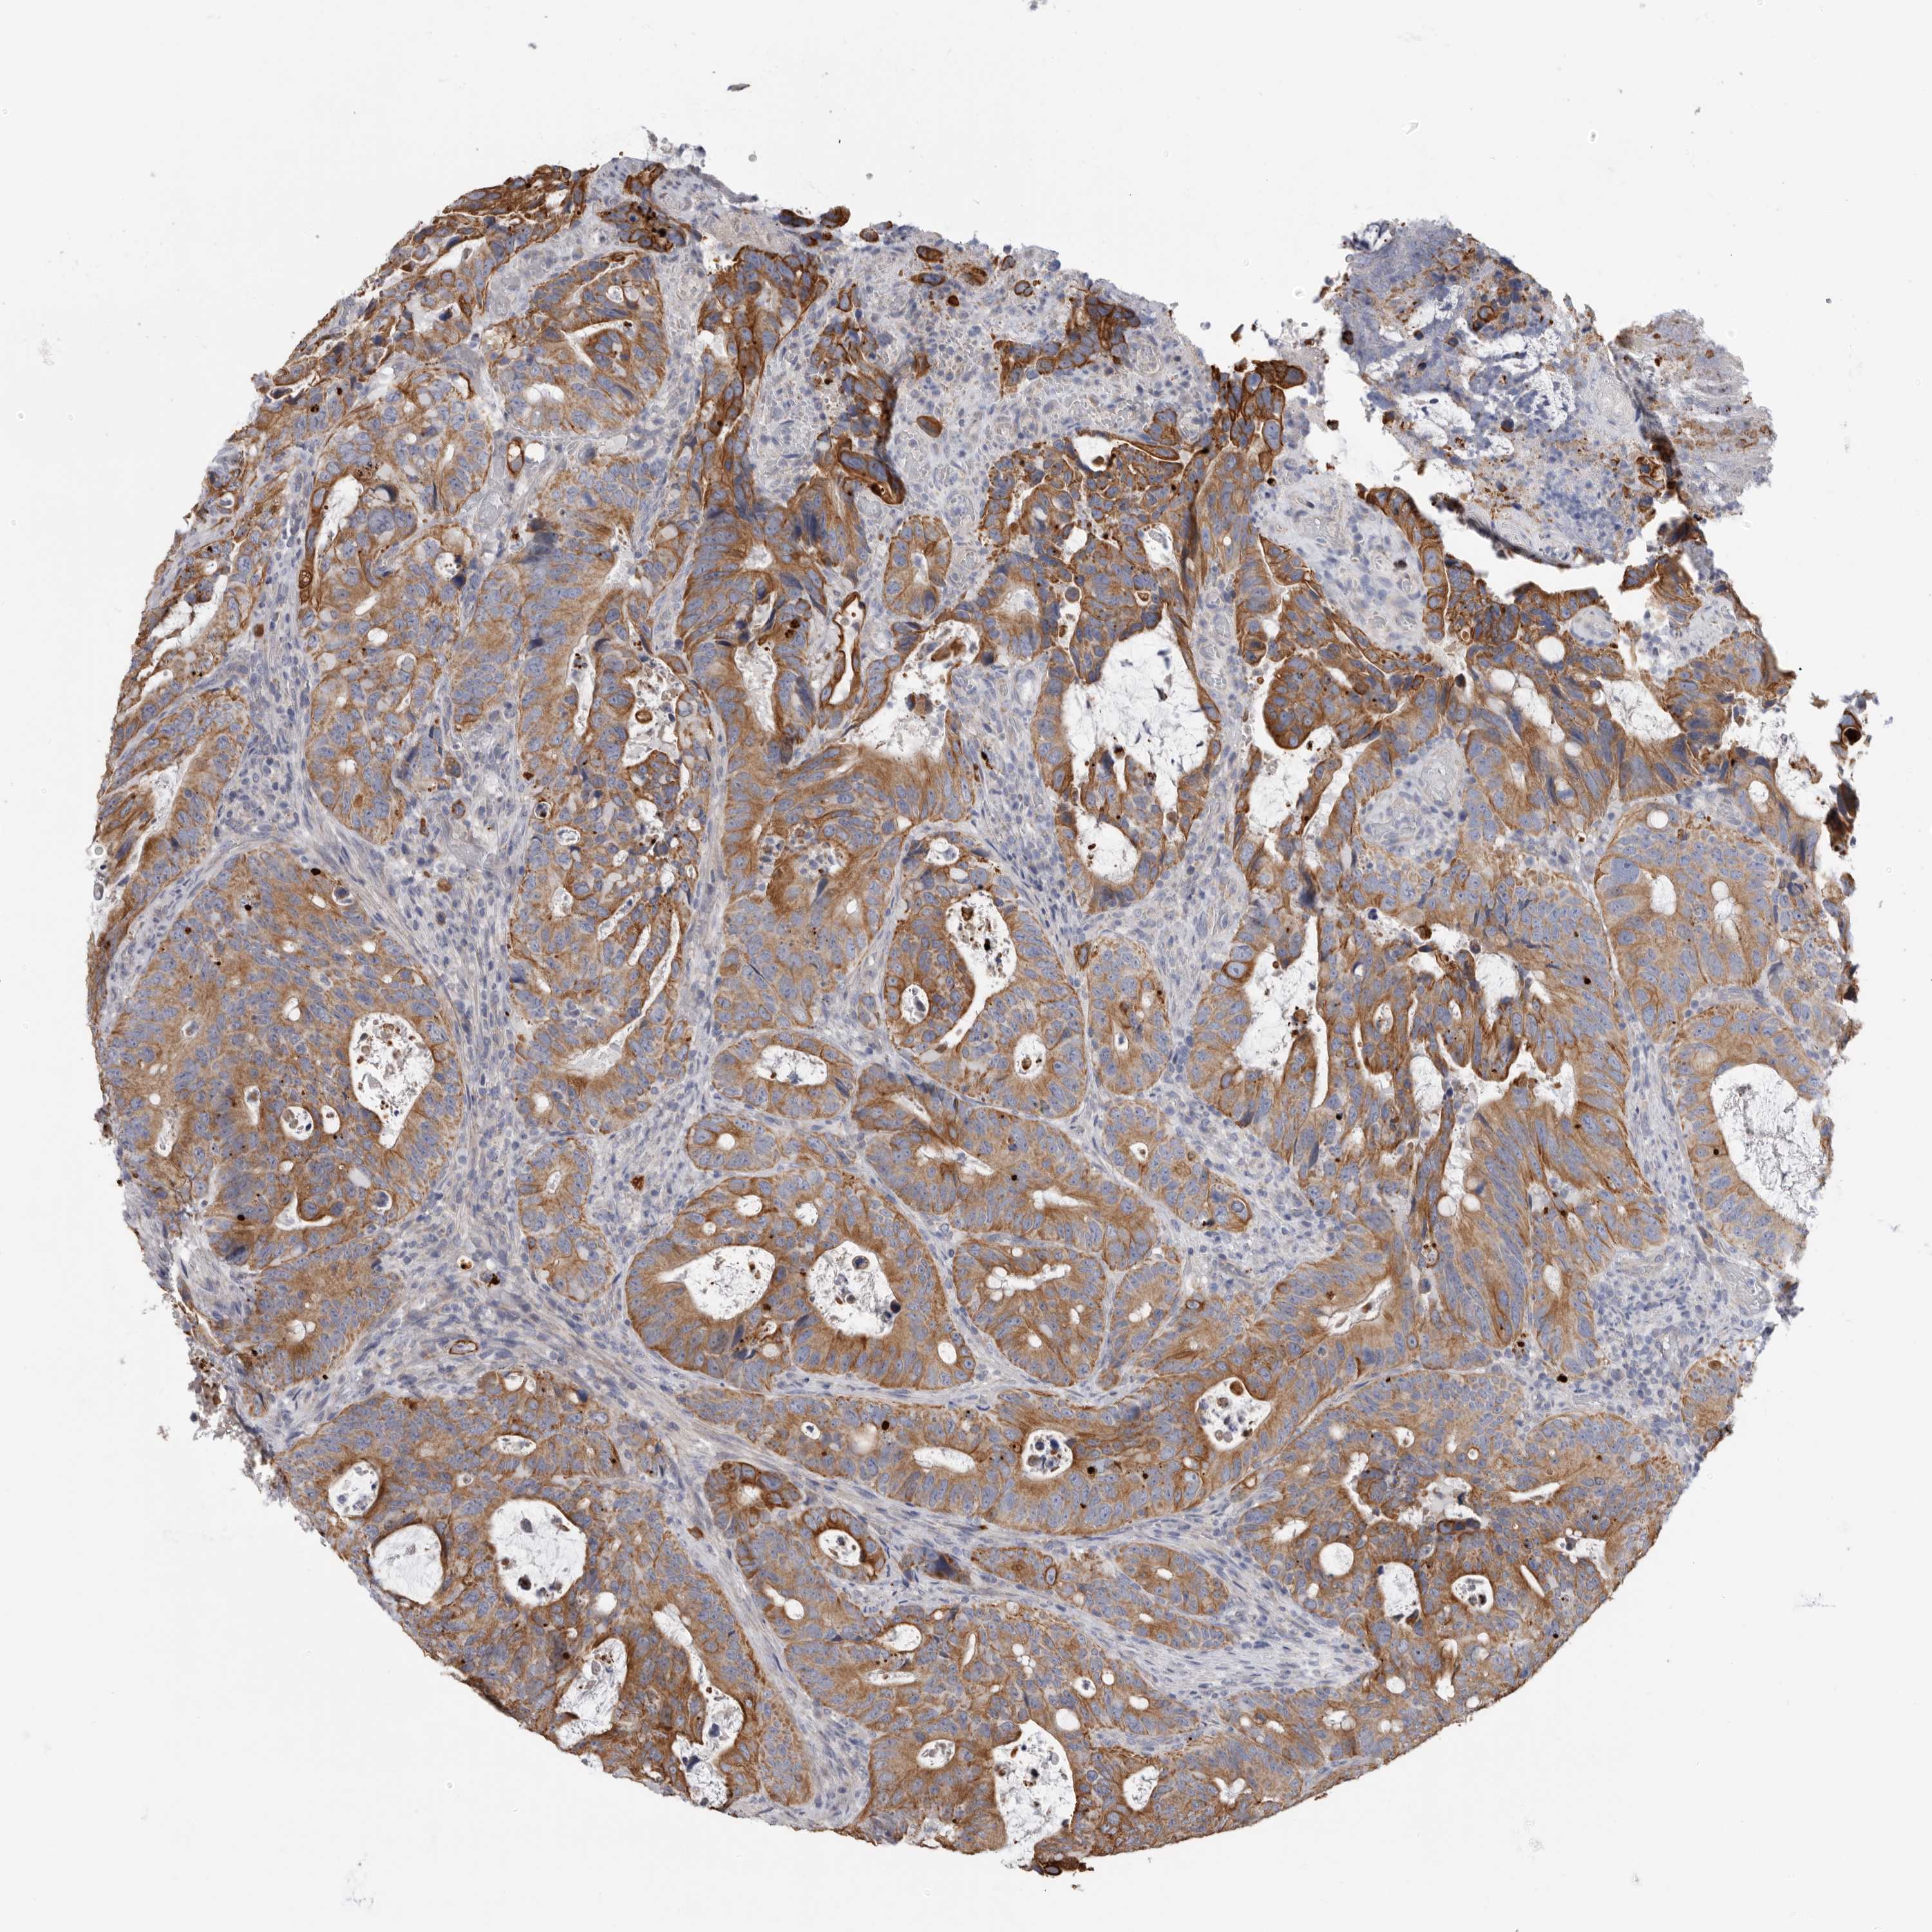

Colorectal cancer

Rectum adenocarcinoma